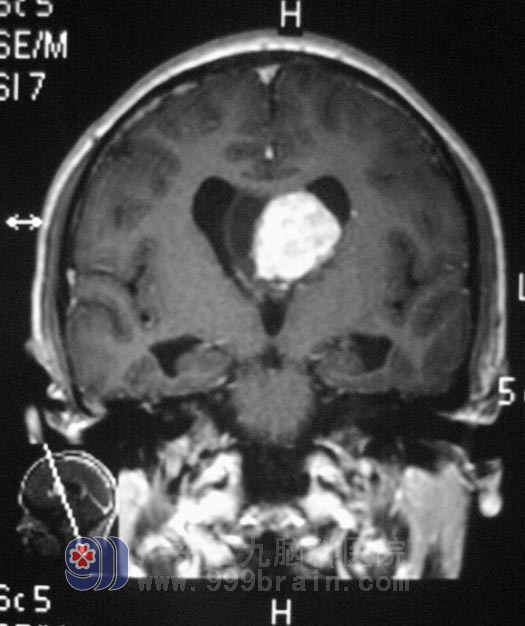

得知儿子得了脑肿瘤,一家人带着小何到处求医,想着儿子风华正茂的年纪,说什么也不能放弃。几经周折,妈妈带着儿子来到广东三九脑科医院找到鲁明主任,门诊查头部MRI报双侧脑室占位性病变,伴梗阻性脑积水。粗侧视力左眼1.0,视野正常,右眼0.3,视野较左眼缩小,左耳听力减退,完善相关检查后,4月21日在全麻下行双侧侧脑室占位切除术,见脑室内灰黄色肿瘤,质中偏软、鱼肉样,内有钙化结节,血运较丰富,显微镜下分块切除肿瘤,肿瘤左侧达左侧丘脑,边界不甚清楚,与脑室壁粘连,内侧至对侧脑室,显微镜下基本全切除肿瘤,手术过程顺利,术后复查CT未见异常,经过一段时间的住院治疗,小何已经康复出院,术后病理结果为:(脑室内)星形胶质细胞瘤,WHOII级。小何后续仍需要行进一步的放疗。http://www.999brain.com/

手术前